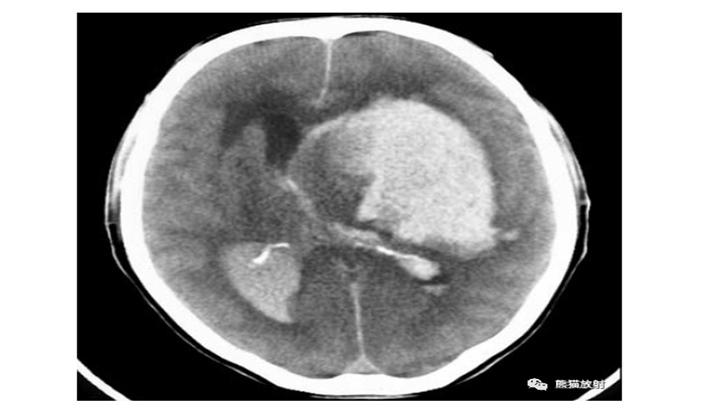

液平面的存在并不罕见(血液在倾斜面处分层)。上图示大的壳核血肿,表现为深部的较新的致密的成分,而其外侧浅表的血肿,以清晰的液-液平面为特征(箭)。下图示一接受抗凝治疗的心脏病发作患者,不规则且广泛分布的多灶性实质内出血中,也可以观察到液-液平面(箭)。